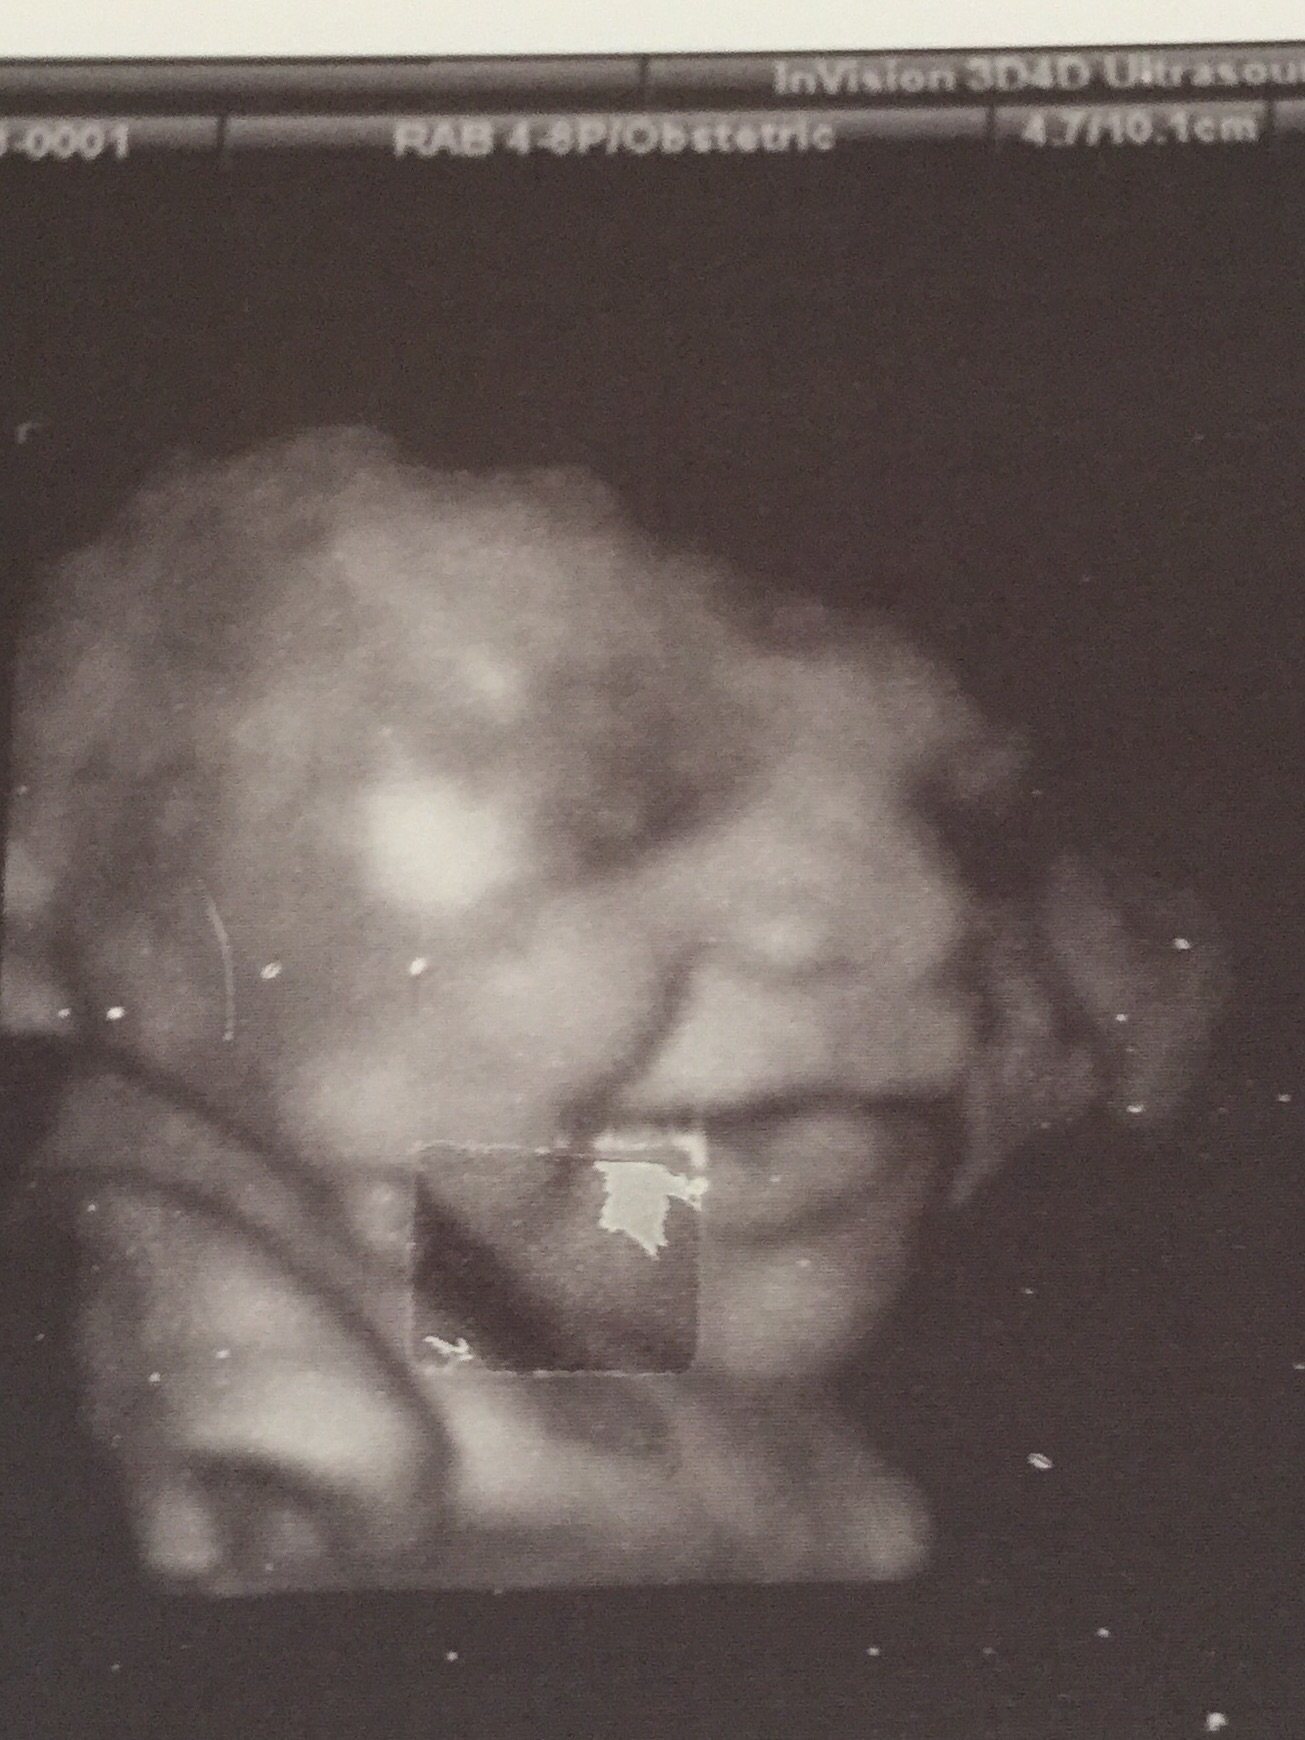

Probably have to be his huge smiles on the ultrasounds ... He just looks so happy in there

This is the greatest ultrasound pic I've ever seen! How adorable. I feel like my baby (team green) at 34 weeks looks Completely annoyed haha.

I think feeling him move for the first time. Really just feeling him move. I love it, even when it hurts. Also our 32 week ultrasound because we got a cool 3D image and it got my husband super excited.